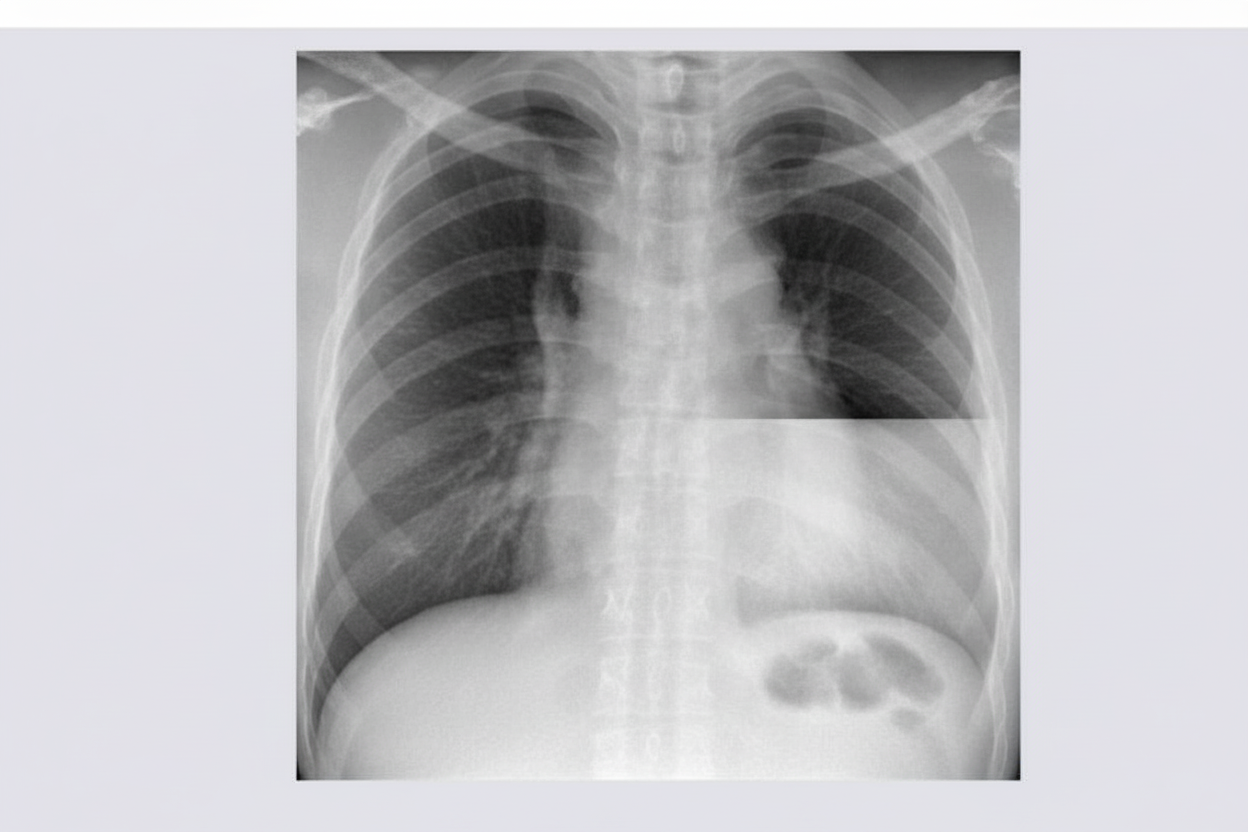

The X-ray provided suggests which of the following conditions?

Explanation: ***Hydropneumothorax*** - Characterized by a classic **horizontal air-fluid level** in the pleural cavity, representing both air and fluid collection. - The **air-fluid interface** appears as a straight horizontal line that changes position with patient positioning, distinguishing it from other conditions. *Normal x-ray* - Would show **clear lung fields** with normal vascular markings and no abnormal densities or air collections. - The presence of an **air-fluid level** clearly indicates pathology, ruling out a normal chest X-ray. *Hydatid cyst* - Appears as a **well-defined, round opacity** with possible **rim calcification** or **water lily sign** if ruptured. - Does not typically present with a **horizontal air-fluid level** unless complicated by secondary infection or rupture into pleural space. *Allergic bronchopulmonary aspergillosis (ABPA)* - Shows **central bronchiectasis** with **finger-in-glove** appearance due to mucoid impaction. - May demonstrate **fleeting pulmonary infiltrates** and **upper lobe predominance**, but not horizontal air-fluid levels in pleural space.